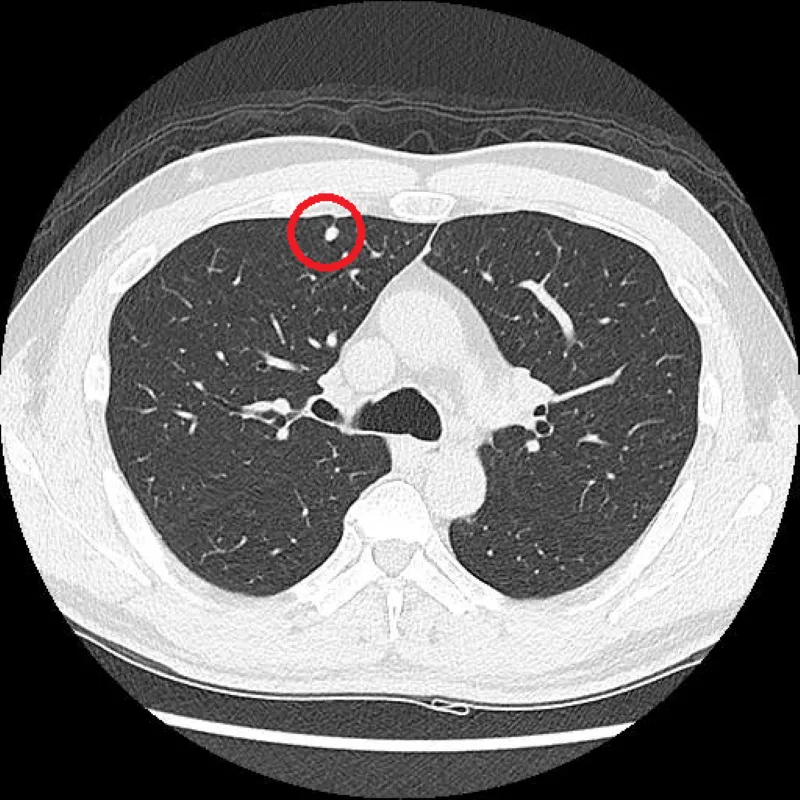

低劑量電腦斷層

LDCT篩檢

肺結節

肺癌

早期發現

電腦斷層染色定位

螢光定位

微創手術

肺癌五年存活率

台北慈濟醫院

肺癌危險因子

肺部結節追蹤

肺腺癌

肺部結節

多發性早期肺癌

複合式手術室

影像導航定位

高風險族群

家族史

豐原醫院

肺癌篩檢